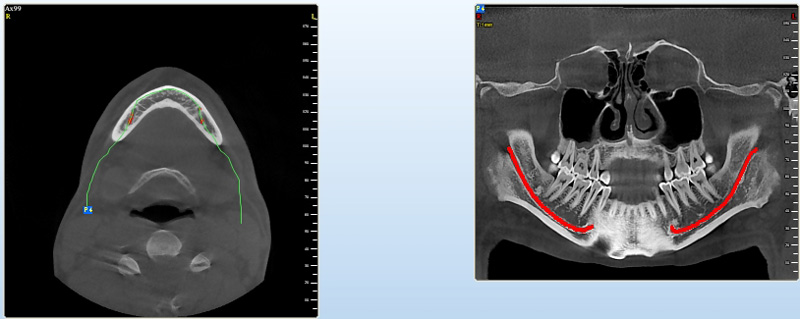

coDiagnostiX – Dental Wings

Jedná se o externí plánovací program, spojený se zubní laboratoří a frézovacím centrem, který využívá dat získaných z 3D rentgenu čelisti, otisku zubů a dásně (scanu zubů a dásně) a finálního návrhu protetické náhrady.

Tento program umožňuje tříprostorovou počítačovou simulaci při plánování pozic implantátů. Součástí programu je i databáze, ve které mohou být uloženy všechny typy implantátů od všech výrobců, včetně jejich délek, průměrů i tvarů.

Lékař si vytvoří všechny typy zobrazení potřebných pro naplánování – tedy 2D snímky (panoramatický), příčné řezy i 3D model.

Vidí zde i důležité anatomické útvary – čelistní dutinu, průběh nervu atd. Po proměření množství kosti – šířky i výšky vybere z databáze vhodný typ implantátu a umístí ho do požadované lokality. Ihned vidí jeho pozici ve všech 3 rovinách a na

všech snímcích i 3D modelu. Může upravovat podle potřeby jeho pozici, sklon atd.

Všechny vybrané a správně umístěné simulované implantáty se ukládají do „počítačové karty“ pacienta s jejich pozicí, délkou, průměrem, typem i sklonem. V programu také lékař navrhuje chirurgické šablony pro řízenou nebo navigovanou implantaci.

Lékař i pacient tedy ještě před vlastní operací vidí, jak by mělo ošetření probíhat a vypadat.